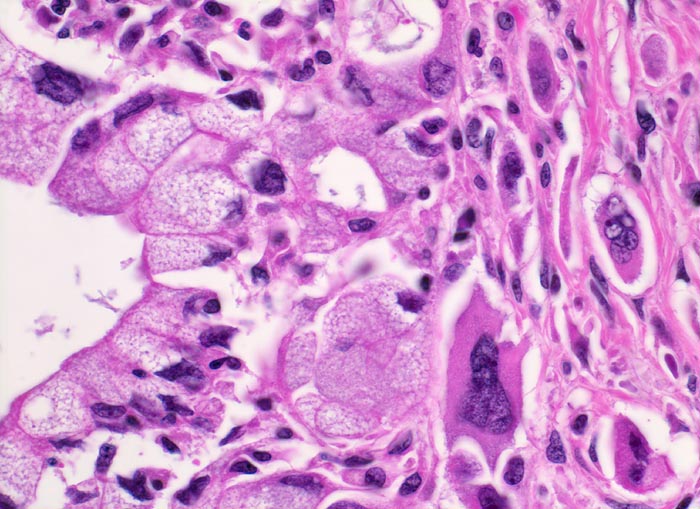

• Unregelmässige Anordnung der Drüsen (keine Läppchenarchitektur erkennbar).

• Kribriforme Drüsenformationen.

• Inkomplette Drüsen mit unvollständigen Lumina und Infiltration des Stromas durch Tumoreinzelzellen.

• Nekrotische Tumorzellen in den Drüsenlumina.

• Ausgeprägte Polymorphie und Hyperchromasie der Tumorzellkerne.

• Desmoplastisches Stroma.

• Rechts oben Reste von nicht neoplastischem Pankreasparenchym mit fokaler chronisch obstruktiver Pankreatitis als Folge von tumorbedingten Gangobstruktionen: Vollständige Atrophie des exokrinen Pankreas bei erhaltenen Inseln. Ersatz des atrophen Parenchyms durch Fibrose. Chronisches Entzündungsinfiltrat.